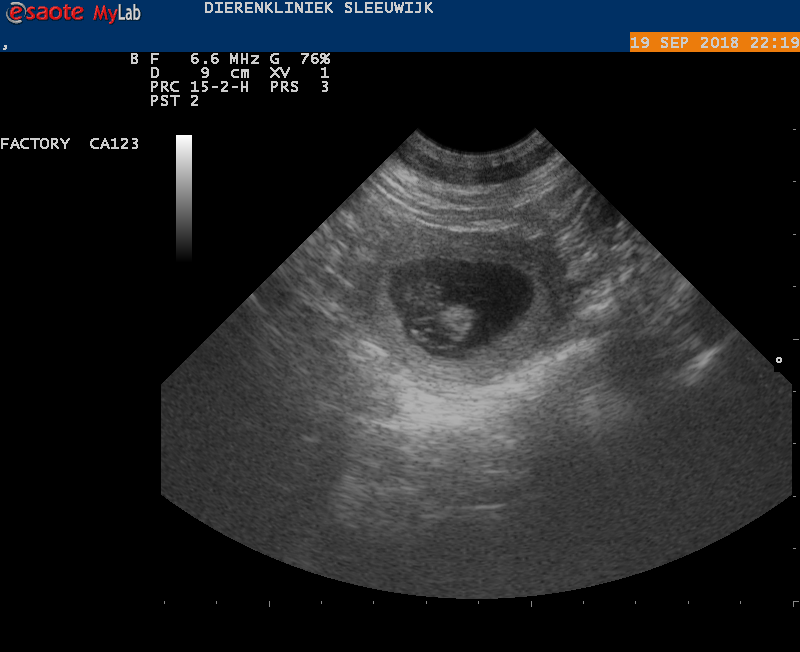

De echo van 20 september 2018